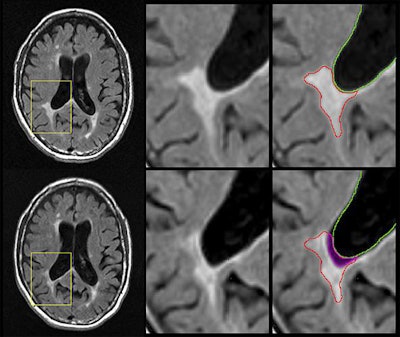

Currently, MS patients undergo MRI scans so clinicians can see whether new lesions are forming or existing lesions are growing. If lesions disappear, it has been considered a sign of improvement.

Three-tesla MRI scans were used to measure lesion volume at the start of the study and through annual follow-up MR imaging for more than five years. The scans revealed that atrophied lesion volume was the only factor that correlated significantly with a change in patient disability (r = 0.192 relapsing MS, r = 0.317 progressive MS, p < 0.05).